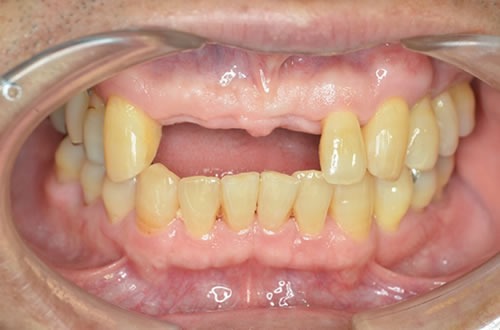

■初診時

前歯の歯がなく、入れ歯を使用しているのですが、固定式(インプラント)を希望され紹介いただきました。